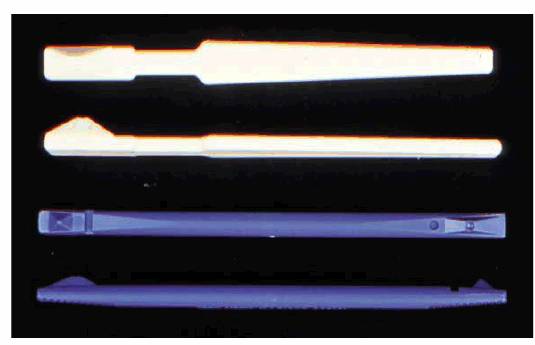

Thermal Pulp Tests

In an effort to determine the vitality of a pulp, the cold test is probably the

most commonly advocated. In the past, an "ice pencil" (water frozen

in sterilized anesthetic cartridge and removed) (Figure 19-11) or an ice cube was the only

consistent way to chill a tooth. But there are several problems with using

frozen water: it is not very cold, so the stimulus may not be intense enough to

penetrate through a porcelain crown, and cold water from the pencil could leak

on adjacent teeth or gingival tissue, giving a false impression of pulpal

vitality in the tooth that is being tested. However, in a tooth with an acute

pulpitis, an ice pencil is an effective diagnostic tool. Recently,

1,1,1,2-tetrafluoroethane has become available in spray form (Endo-Ice,

Hygenic,

Dry ice cylinders (Odontotest Thermal Pulp Tester, Miltex,

Figure 19-11: An ice pencil being applied to a maxillary central incisor tooth.

Figure 19-12: Endo-Ice (Hygenic) refrigerant.